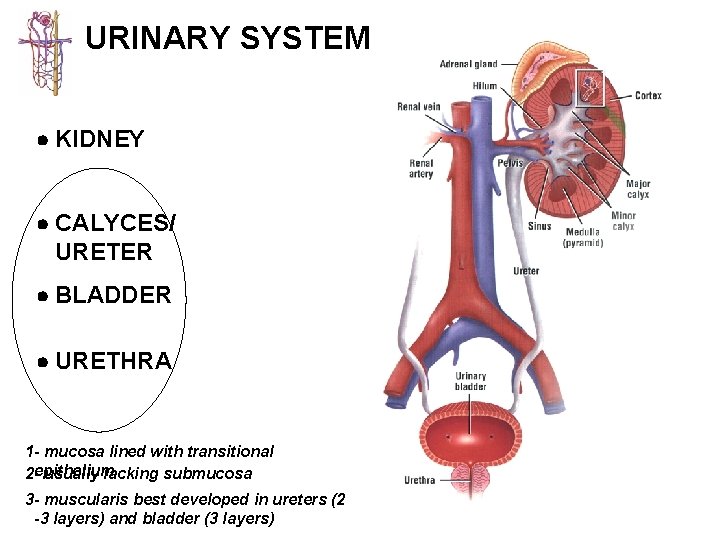

URINARY SYSTEM KIDNEY CALYCES/ URETER BLADDER URETHRA 1 - mucosa lined with transitional 2 -epithelium usually lacking submucosa 3 - muscularis best developed in ureters (2 -3 layers) and bladder (3 layers)

URETER H&E 1: 2: OC IL MUCOSA LAMINA PROPRIA MUSCULARIS ADV

URINARY SYSTEM URETER

URINARY SYSTEM URETER